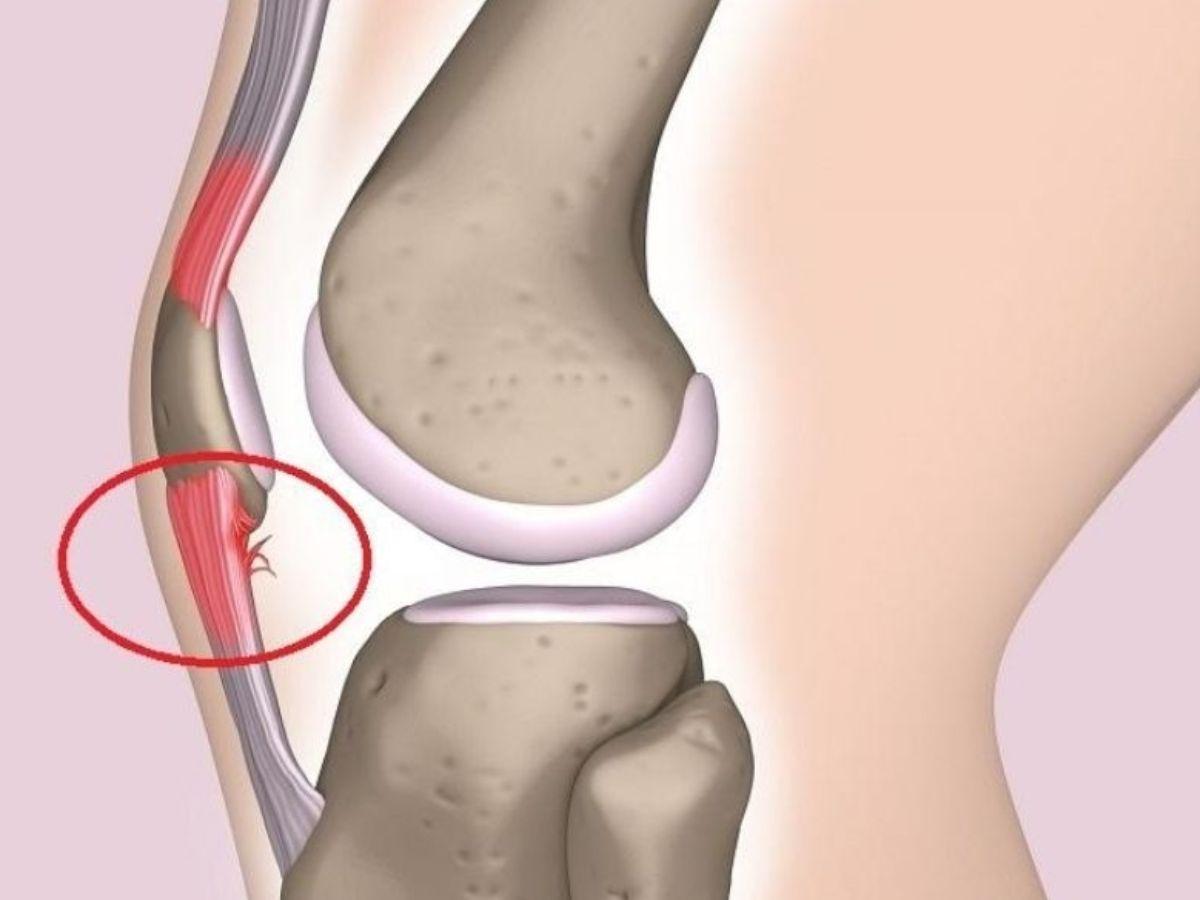

Hội chứng dải chậu chày

Hội chứng dải chậu chày là tình trạng viêm khớp dải chậu chày do vận động quá thường xuyên nhưchạy bộ hoặc căng thẳng thần kinh. Triệu chứng ban đầu là cảm giác đau bên ngoài khớp, có cảm giác đau đớn hơn khi co gập chân hoặc di chuyển đường dài. Cơn đau tăng dần khi vận động mạnh và có thể đau lan lên khu vực hông và xương chậu.

Viêm khớp dải chậu chày (Nguồn: Phiten Việt Nam)